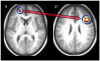

Reality monitoring refers to the process of discriminating between internally and externally generated information. Two different tasks have often been used to assess this ability: (a) memory for perceived versus imagined stimuli; and (b) memory for participant- versus experimenter-performed operations. However, it is not known whether these two reality monitoring tasks share neural substrates. The present study involved use of a within-subjects functional magnetic resonance imaging design to examine common and distinct brain mechanisms associated with the two reality monitoring conditions. The sole difference between the two lay in greater activation in the medial anterior prefrontal cortex when recollecting whether the participant or the experimenter had carried out an operation during prior encoding as compared to recollecting whether an item had been perceived or imagined. This region has previously been linked with attending to mental states. Task differences were also reflected in the nature of functional connectivity relationships between the medial anterior and right lateral prefrontal cortex: There was a stronger correlation in activity between the two regions during recollection of self/experimenter context. This indicates a role for the medial anterior prefrontal cortex in the monitoring of retrieved information relating to internal or external aspects of context. Finally, given the importance of reality monitoring to understanding psychotic symptoms, brain activity was related to measures of proneness to psychosis and schizotypal traits. The observation of significant correlations between reduced medial anterior prefrontal signal and scores on such measures corroborates these theoretical links.